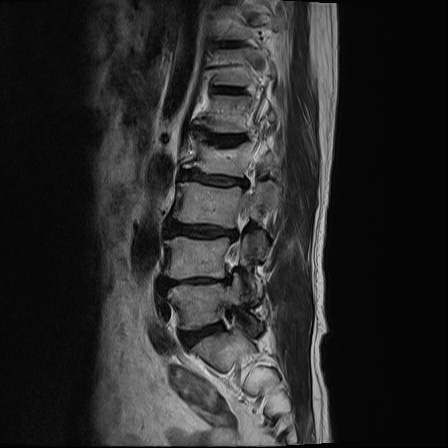

Ӵϲ ɿ ô ô 㸮 ٸ ̾ϴ. ϵ Ͻð ܻ 㸮 20⵿ ͽϴ. mri ˻ ɿ Ȳ ʹ ؼ Ȳ̶ ߽ϴ. ϻȰ ϰ 鼭 ½ϴ. ̴ ø鼭 Ͻô Ȳ ̷ ġ ص ȸ ϴ. δ Ҵµ, ù ȸԲ ˷ֽ ϰ β ϰ, ˷ֽ ü ƮĪ ϸ鼭 ȭǸ鼭 Ӵϲ ȸų ְ ǰ, β 鼭 ʴ β ؾϴ ŷο 1ϸ ijħ ڸ ǥ Ʈ ߽ϴ. ȸ ȭϽø鼭 Ϸ簡 ٸ ȸǽð 4ְ Ǿ Ǯ鼭 ¦ ҽϴ. ħ ȸ ȭϸ鼭 ڼ ü ƮĪ ϴ. ȥڼ Ͻʴϴ. ٳø鼭 ó Ͻ ʴϴ. ̾ ְ ̳ ߵ ʰ ϴ ȸԲ Ͻʴϴ. ʹ ϸ鼭 ϴ. Ȩ - ϱ ٴ Ȳ MRIԴϴ. |